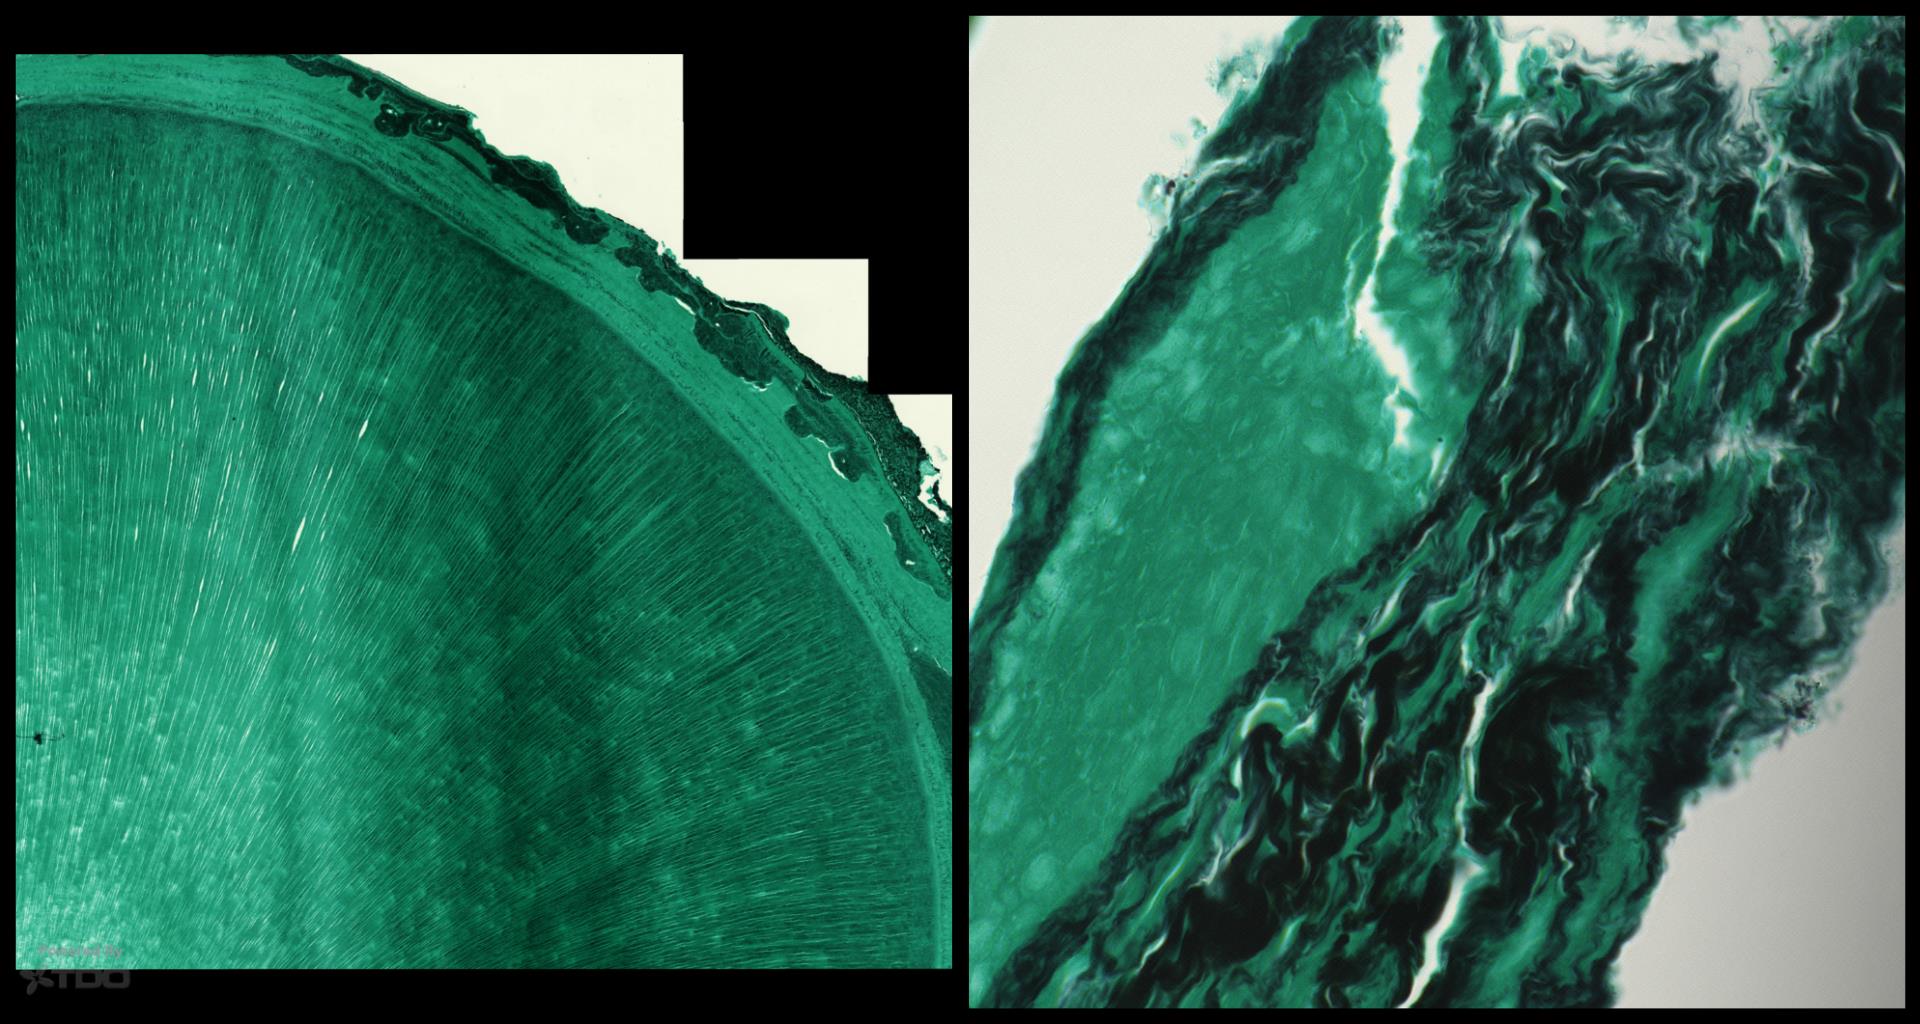

I took John’s root tip he sent me and processed it as follows: 1. Decalcified the root in EDTA for 1 week then some Decal overnight (Formic aa) 2. Mounted in parrafin for standad H&E staining. 3. Sectioned the tooth axially every 100 microns until exhaustion. 4. Every 100 microns an H&E stain was done, A Brown-Brenn stain was done, and a Fungal stain was done. 5. All 60 slides were scanned at 200x, and 600x. Two representative sections are shown here. Initial impressions: 1. No lateral canals were detected in any of the slices. 2. No bacterial colonization was detected in any of the B-B stained slides 3. There was a suggestion of fungal colonization on the external root surface 4. The pulpal space had minimal, if any, bacterial morphotypes evident. Open to alternative impresions from others. The last (page 7) slide shows the control slide for the Brown-Brenn bacterial stain. gbc Ain’t the Collage function awesome…..